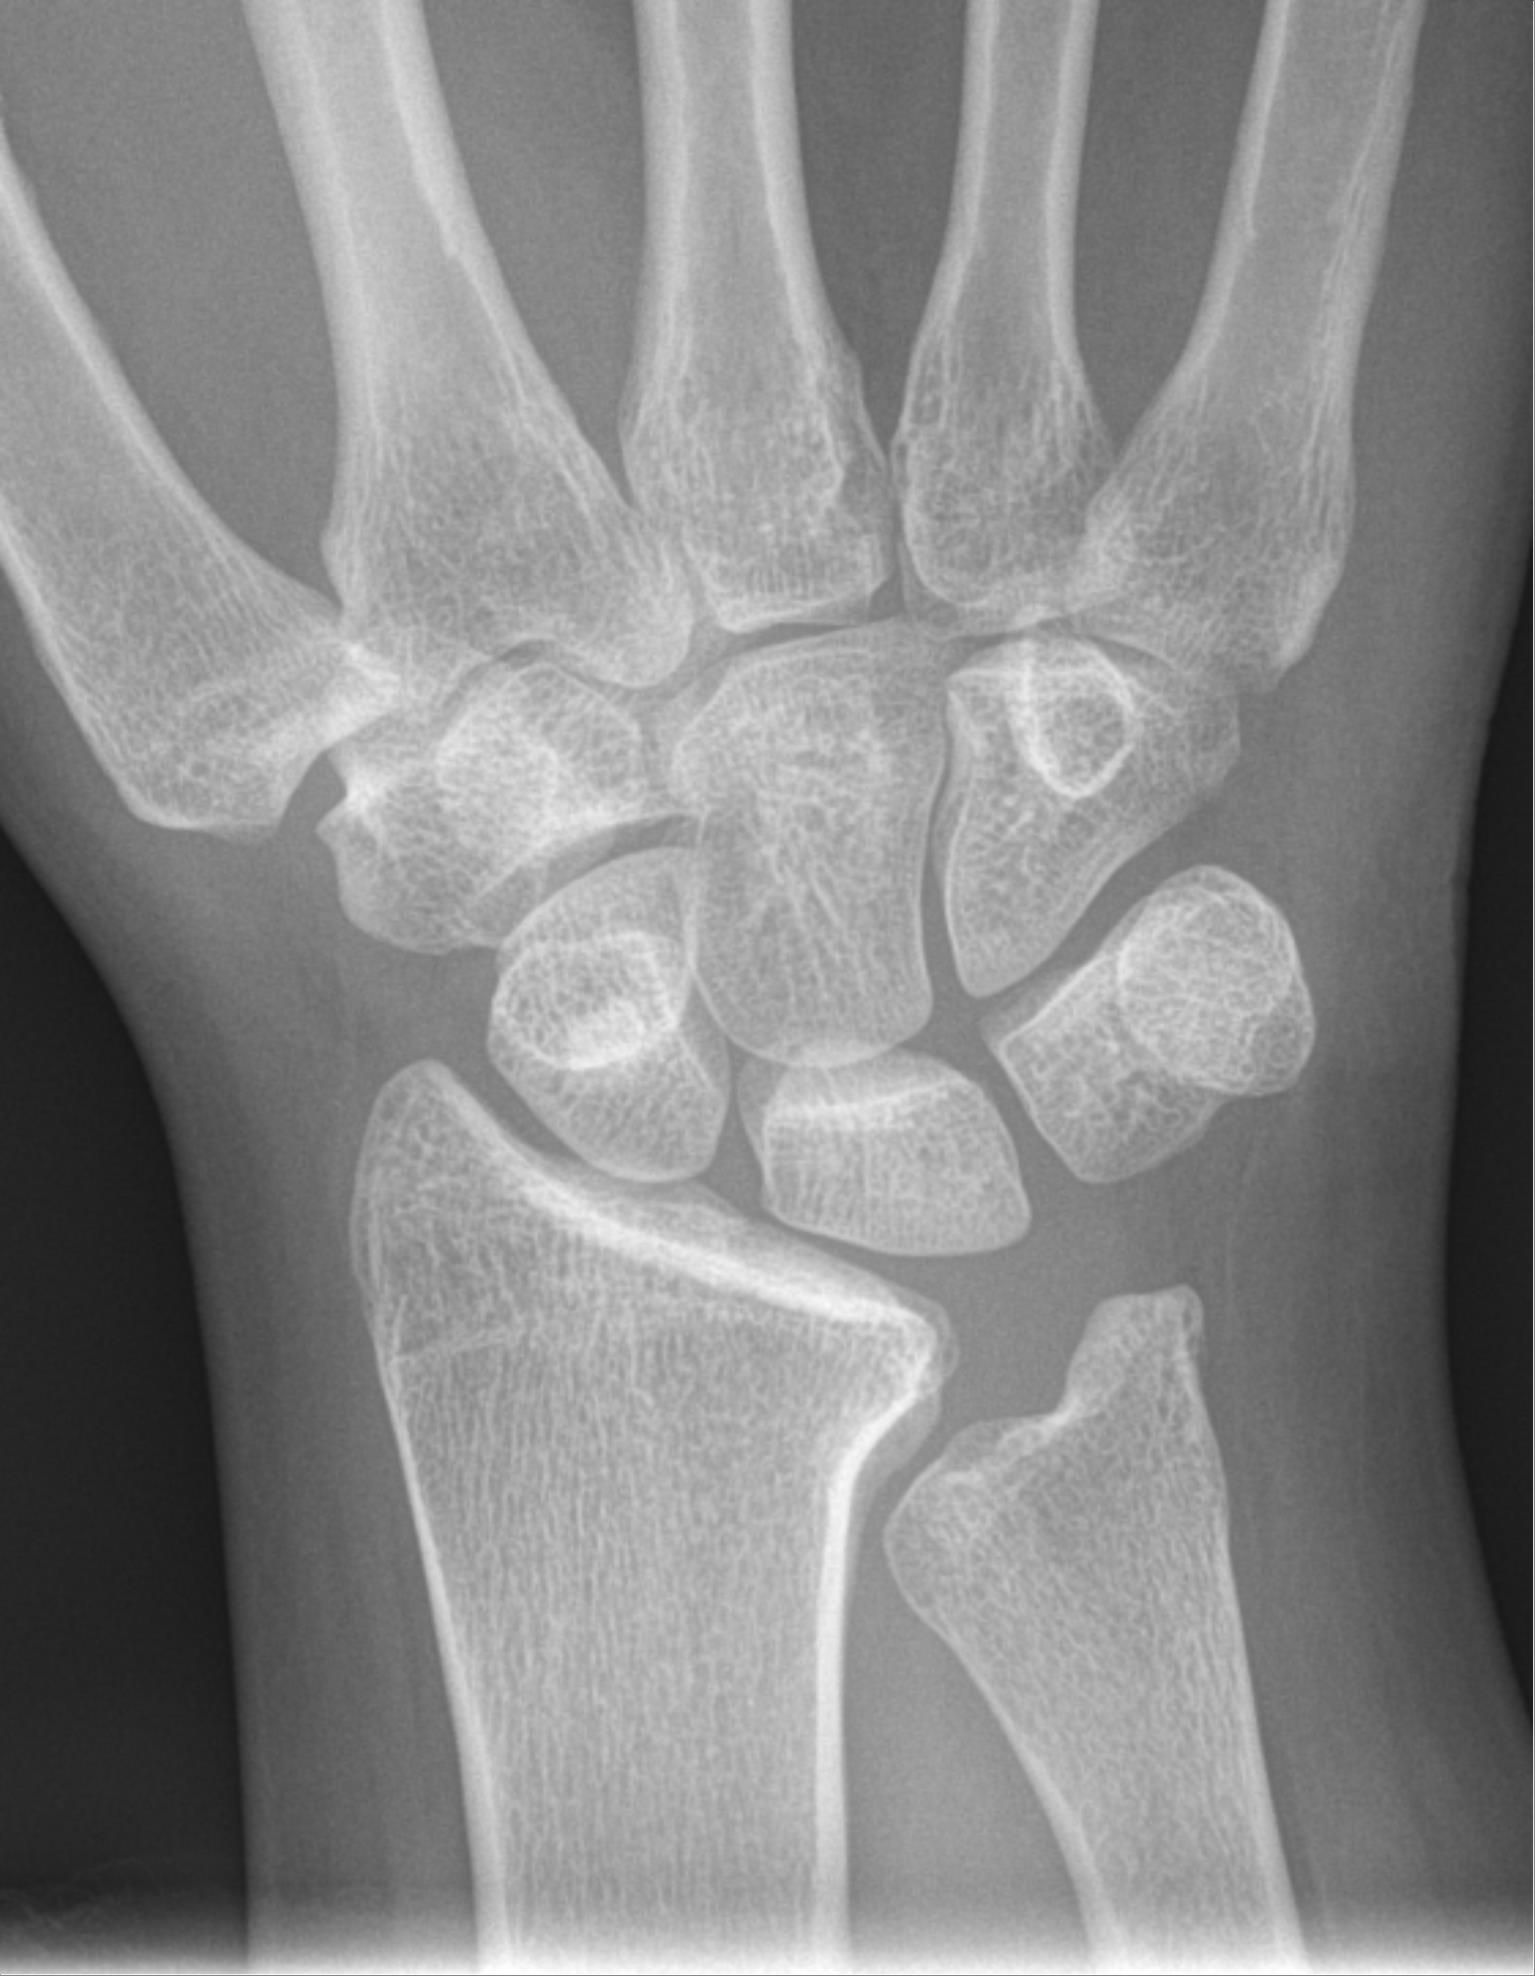

La osteonecrosis del semilunar o Enfermedad de Kienböck, aunque no es excesivamente frecuente, refleja una seria problemática en la vida y el futuro de nuestros trabajadores, condicionando siempre problemas laborales, sociales e incluso médico-legales. En Viena, en 1910, el joven radiólogo Robert Kienböck publicó la que sería una de las más lúcidas descripciones de la enfermedad denominada en aquel entonces lunatomalacia escribiendo «que existe una lesión característica del semilunar, probablemente debida a una contusión o esguince, que desencadena un trastorno en la nutrición del hueso que lo debilita. Ello suele evidenciarse en forma de esclerosis y una gradual descomposición de su polo proximal, quien acaba fragmentándose»; descripción muy afortunada, ciertamente cuya esencia sigue inalterada casi un siglo más tarde.

Kienböck’s disease is a problema in the wrist casued by the loss of blood supply to the lunate. The lunate is one of the eight small bones that make up the “carpal bones” in the wrist. There are two rows of bones: one closer to the forearm, the “proximal row;” the other closer to the fingers, the “distal row.” The lunate bone is the center of the proximal row. It is next to the scaphoid bone, which spans the two rows.

La etiología de la enfermedad de Kienböck (EK) es desconocida; se piensa que se debe a una pérdida de flujo sanguíneo en el hueso semilunar (Se), generalmente atribuida a la presencia de problemas circulatorios primarios. Es una patología muy restrictiva a veces, debido al dolor y a la limitación funcional de la mano que causa.

Kienböck’s disease affects the lunate bone in patients who are usually in their twenties, and present with pain, swelling and stiffness of the wrist. Almost every treatment currently suggested for Kienböck’s disease is based on an hypothesis rather than proven knowledge.